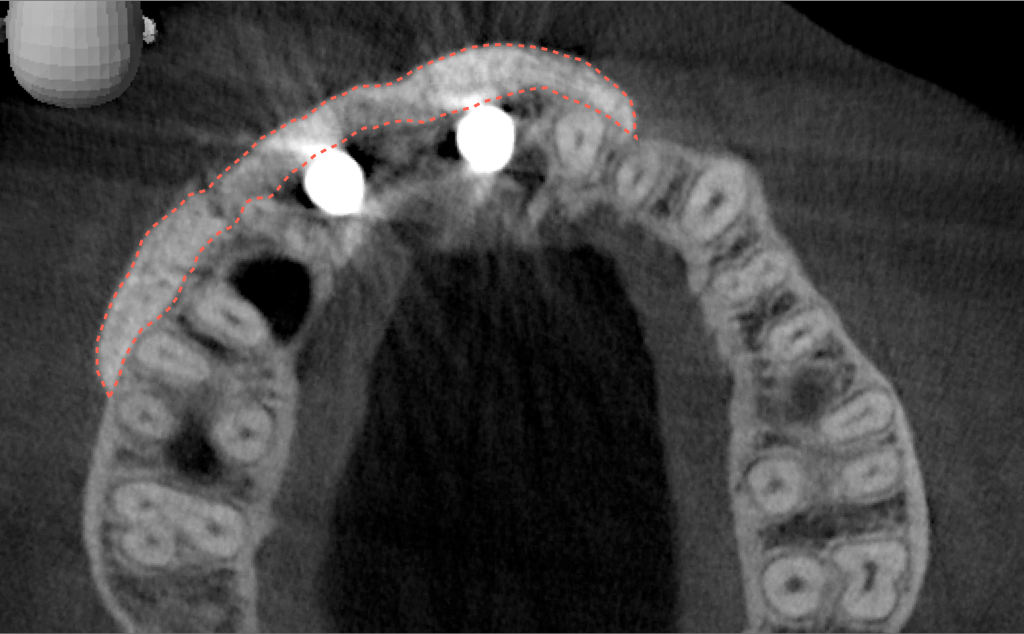

Tomographic images revealed a large tridimensional defect, with vertical and horizontal loss of bone extending to the apical third of teeth Nos. 6 and 8. Additionally, a buccal bone dehiscence was evident on tooth No. 5, and thin labial plates secondary to the orthodontic movement were present in several areas (Figure 3 and Figure 4).

After 3 months of post-orthodontic stabilization, a cone-beam computed tomography scan was taken to re-evaluate the results and plan the future treatment sequence. Tomographic images clearly showed vertical gains in alveolar height, including in the edentulous area corresponding to tooth No. 7 (Figure 10 through Figure 12). The apex of tooth No. 8 was forced-erupted beyond its socket and could be visibly located within the soft tissue.30,33

Fig 10. Tomographic images of teeth Nos. 6 (Fig 10), 7 (Fig 11), and 8 (Fig 12) clearly showed vertical gains in alveolar height, including in the edentulous area corresponding to tooth No. 7. The apex of tooth No. 8 was located within the soft tissue because it was force-erupted beyond its socket.

Fig 11. Tomographic images of teeth Nos. 6 (Fig 10), 7 (Fig 11), and 8 (Fig 12) clearly showed vertical gains in alveolar height, including in the edentulous area corresponding to tooth No. 7. The apex of tooth No. 8 was located within the soft tissue because it was force-erupted beyond its socket.

Figure 11

Fig 12. Tomographic images of teeth Nos. 6 (Fig 10), 7 (Fig 11), and 8 (Fig 12) clearly showed vertical gains in alveolar height, including in the edentulous area corresponding to tooth No. 7. The apex of tooth No. 8 was located within the soft tissue because it was force-erupted beyond its socket.

Figure 12